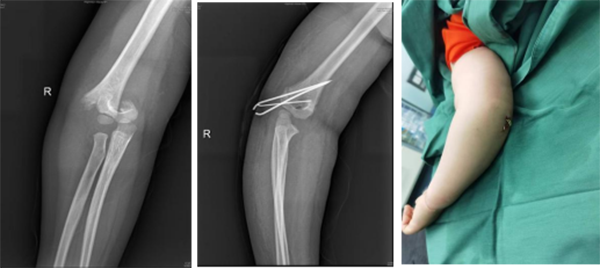

徐醫(yī)附院小兒骨科依托省級臨床重點?乒强破脚_,擁有雄厚的醫(yī)療、科研實力,配備了脊柱手術(shù)顯微鏡、術(shù)中導航、脊柱微創(chuàng)內(nèi)鏡、關(guān)節(jié)鏡設備、術(shù)中神經(jīng)電生理監(jiān)測、超聲骨刀等先進設備,極大地保證了患兒高難手術(shù)的精準性和安全性。自2022年2月17日成立以來,徐醫(yī)附院小兒骨科秉承“微創(chuàng)化、精準化”的治療原則,為淮海經(jīng)濟區(qū)兒童骨科患者提供優(yōu)質(zhì)的醫(yī)療服務,贏得了廣泛贊譽。當前,徐醫(yī)附院小兒骨科每月完成手術(shù)近40余臺。小兒肱骨髁上骨折、前臂骨折、股骨干骨折等常見骨折基本上都是經(jīng)皮微創(chuàng)完成,獲得患兒家長的好評和信任。